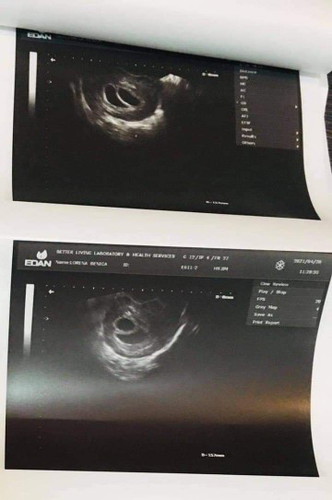

8 weeks Gestational Sac

Good day po..ask ko lang po possible po ba na in 8 weeks po hindi pa din po makita ang baby na twins po sa TVS. Gestational sac palang po nakikita sa ultrasound ,mga ilan weeks po ba dapat mag pa TVS para makita na heartbeat? Pero ang bilang po kasi ng weeks ko from LMP is 7weeks po.. pero sa TVS 8weeks na daw po baby ko. #1stimemom #firstbaby #pregnancy #pleasehelp